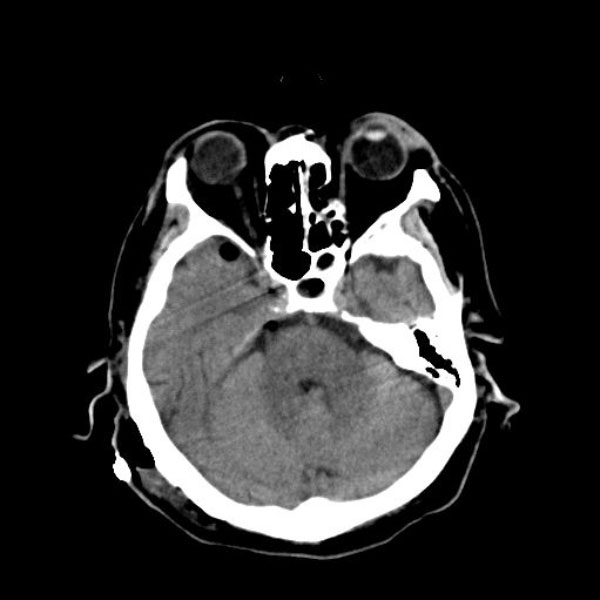

手術前

(MR1)

手術後

(CT)